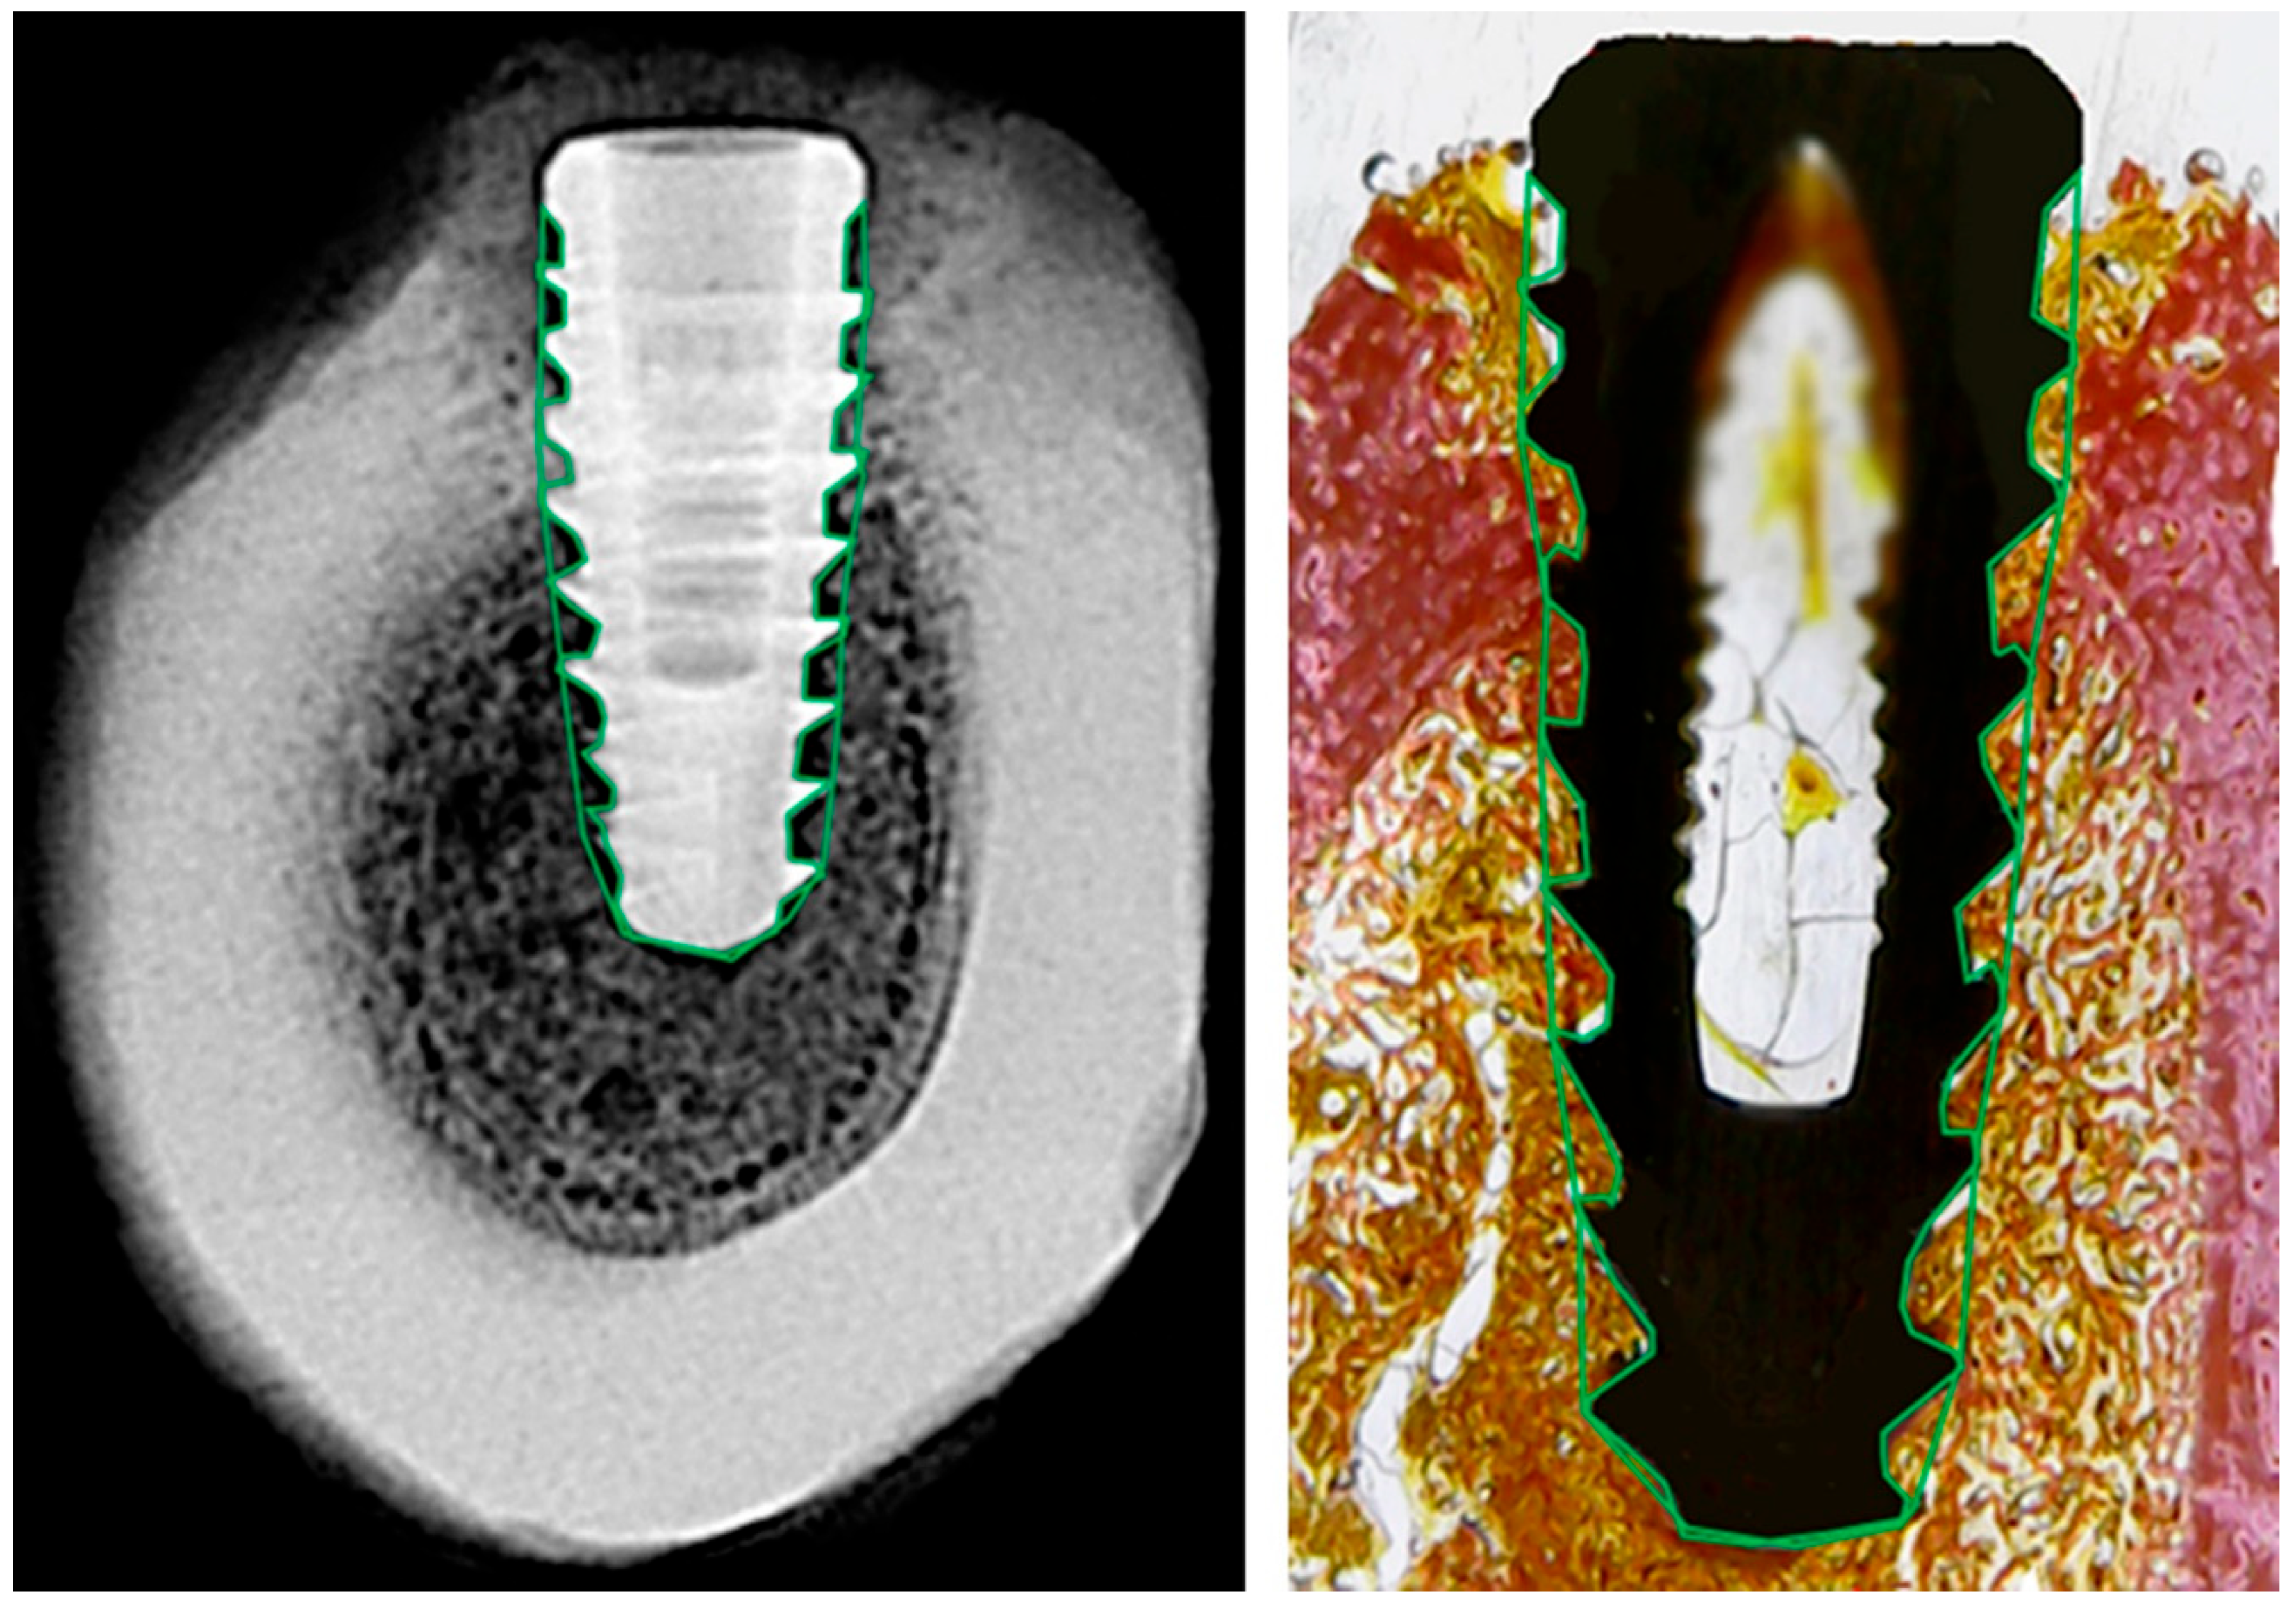

2.9. Histological Parameters’ Evaluation

Histomorphometric analysis was performed using Fiji/ImageJ, with the software calibrated based on implant dimensions. The total area around each implant within each thread (Figure 3, right) was defined and considered as 100%. Then, using higher-magnification images, the relative areas occupied by collagen tissue, bone tissue, and marrow space were measured. The results are expressed as percentage values of total area, as illustrated in Figure 5.

Figure 5. Representative histological image illustrating tissue segmentation using Fiji/ImageJ. In this example, the green-outlined region represents bone tissue (pink area). Collagenous tissue is identified in orange, and the medullary space appears as white. The software was calibrated using the known dimensions of the implant, and the relative areas of each tissue type were measured within predefined regions of interest.